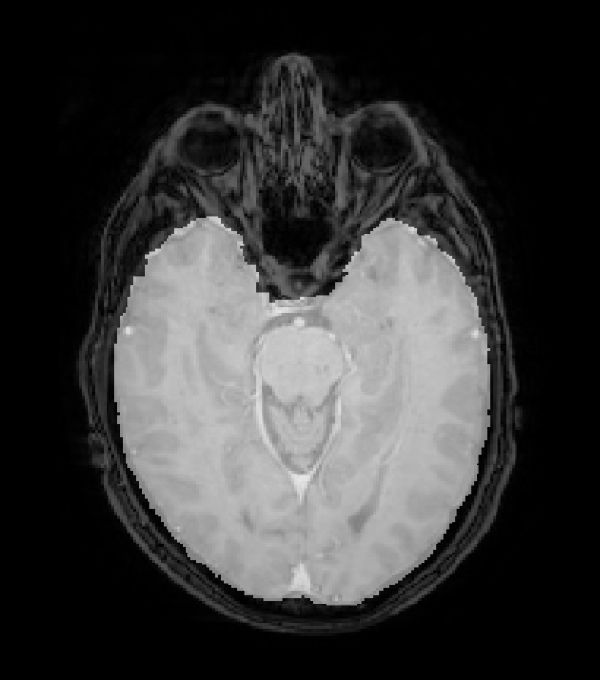

Image: MRI of a healthy HUNT participant. Women with large brains have a greater risk of developing a brain tumour compared to men with a big brain. (Photo: Even Hovig Fyllingen)